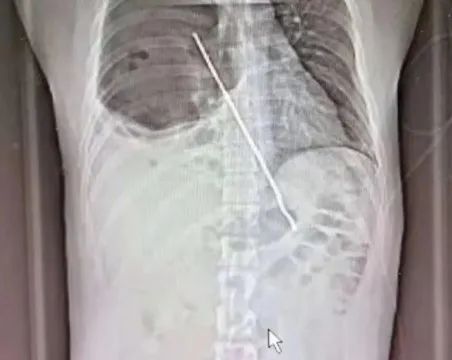

西安醫(yī)學院第一附屬醫(yī)院急診科接診后,發(fā)現(xiàn)張先生不是一般情況的腹痛表現(xiàn),于是對其緊急進行胸部CT及全腹部CT檢查,圖像顯示,一根長約20cm的鐵簽穿破小張的食管壁并刺入右肺。

CT檢查結(jié)果顯示,長約20cm的鐵簽已經(jīng)穿破他的食管壁并刺入右肺。